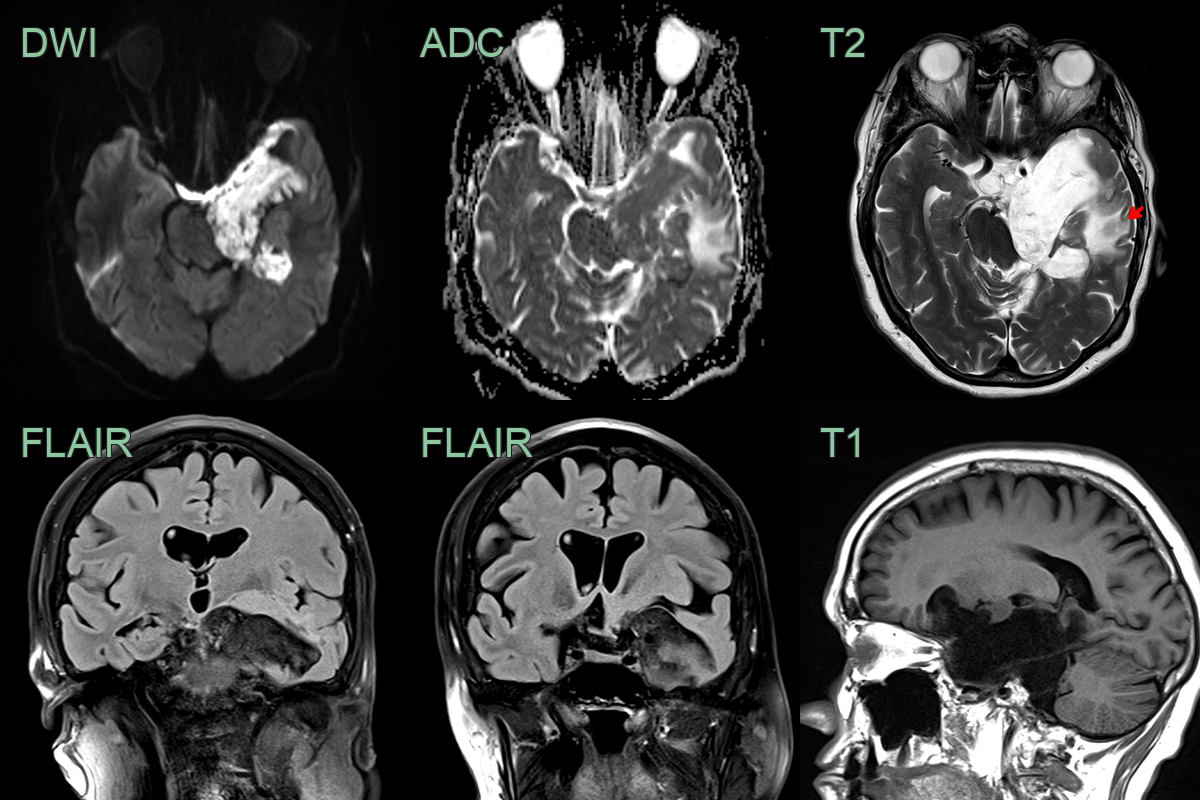

- MRI:

- T1: Hypointense to isointense

- T2: Hyperintense

- FLAIR: Heterogeneous signal intensity

- DWI: Marked restriction (key diagnostic feature)

- No enhancement with gadolinium

- "Popcorn" appearance on DWI due to lamellated keratin

- 60-year-old patient present with ataxia and poor left-sided hearing.

- MRI showed a T2-hyperintense non-enhancing lobulated lesion with low ADC values in the left side of the posterior fossa, encasing the 7th and 8th nerve complexes.

- There was significant mass effect on the cerebellum (presumably relevant to the ataxia) but there was no oedema, indicating that this lesion has grown slowly.